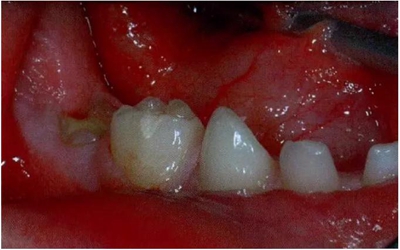

圖2:中度下沉的臨床像

臨床檢查看到合平面出現(xiàn)擾動可做為診斷依據(jù)。下沉乳磨牙位于合平面的凸起端(圖4)。這些牙齒在使用金屬器具敲擊時,會發(fā)出典型的高調(diào),固連“有裂紋茶杯”聲。同時還需要做影像學檢查,以確認繼承恒磨牙是否缺失。

圖4:由于乳牙下沉而導致合平面發(fā)生改變的臨床像